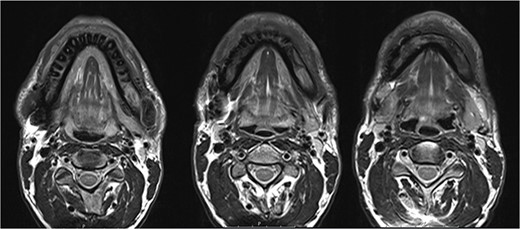

In 2020, a 99 m Technetium scintigraphy was performed to rule out disseminated osteomyelitis. The scintigraphy showed no other foci of enhancement but the mandible with increased inflammatory activity in the anterior portion of the jaw (Fig. 1). Magnetic resonance imaging (MRI) was performed to analyze the localization and extent of the disease. In Fig. 2, a high inflammatory activity, resembled by a strong local enhancement in the T2 weighting, was seen, reaching from the right condyle to the left. Cone beam computed tomography (CBCT) confirmed a widespread patchy radiolucency extending to both left and right mandibular condyles (Fig. 3). Hard tissue biopsies were taken to rule out malignancy due to the disease’s extensive destruction and chronic course. Blood assays were also requested.

Magnetic resonance imaging (MRI) before bisphosphonate therapy (axial sections). T2 weighting of the MRI shows the high inflammatory activity especially in the anterior portion of the mandible (arrow).